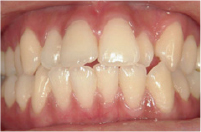

| 初診時年齢 | 23歳 |

|---|---|

| 主訴 | 口元が出ているのが気になる |

| 診断名 | 叢生を伴う上顎前突 |

| 治療に用いた装置 | リンガルブラケット矯正装置 |

| 抜歯部位 | 上下左右4番抜歯 |

| 治療期間 | 2年3ヶ月 |

| 費用の目安 | 約800,000円 |

| リスク副作用 |

治療前

治療後